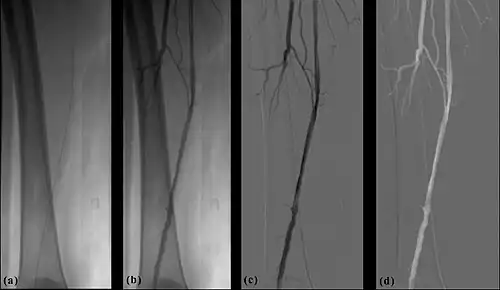

- Image noise can also be reduced using the DSA image processor. This is achieved by applying image averaging processes to the sequence of angiography images following computer acquisition and before subtraction. The simplest form of image averaging involves summing a number of images together and dividing by that number. It can be shown, based on statistical considerations, that this process reduces noise ideally by a factor of √N, where N is the number of averaged images. Thus, to double the SNR, four images should be averaged. SNR improvement can also be achieved by integrating (i.e. adding) images and by recursive filtration. This latter process can involve the application of an exponentially-weighted moving average process to angiographic image sequences. It can be shown that such filtering is more powerful than simple averaging and can give a theoretical SNR improvement of √(2N-1). Note that this type of filtering can also be applied for screening exposures providing what is sometimes referred to as Fluoro Noise Reduction (FNR). Digital noise reduction techniques are generally performed using the Image ALU component of the DSA image processor.

- The temporal-averaging feature of digital noise reduction can also be used for image presentation purposes so that the time course of the movement of contrast medium during a study can be displayed using just one image - see an example in Figure 7.4 from the peripheral study shown above - instead of a sequence of numerous images. Such an image is sometimes referred to as a Vascular Trace.

- One method of temporal filtration, referred to as Integrated Mask-Mode DSA involves adding (also called integrating) a number of images, acquired prior to the arrival of the contrast medium, to form an integrated mask image and adding a number of peak-opacification images to form an integrated live image. This is the process that was used to generate the vascular trace image in Figure 7.4. Thus, when four images are used to generate each integrated mask and live images, eight of the 25 images are now used in the subtraction process and, as a result, only 68% of the dose is wasted, and a subtraction image with lower noise results.

- Additional processes involve Bolus Chasing, Rotational Angiography and Volume Tomographic Angiography. Bolus Chasing[28] has been found to be particularly helpful in peripheral angiography, for example. Here, the progress of the contrast medium is tracked automatically and used to increment the table and/or XRT/image receptor movement to the next anatomical region. The subsequent set of subtraction images can then be used to construct a composite image of the peripheral vasculature. In Rotational Angiography[29], a C-arm assembly, for example, can be caused to rotate at 10 - 30 degrees per second during the imaging sequence. Subsequent dynamic display of the subtraction images can be used to generate a perceived 3D presentation so that complex relationships within the vasculature can be more readily appreciated. Volume Tomographic Angiography[30] is similar to Computed Tomography (CT) where the C-arm is rotated around the patient during the imaging sequence. The image data is subject to a volume reconstruction algorithm which permits generation of three-dimensional images of the opacified vasculature. We will consider this latter process in more detail below.